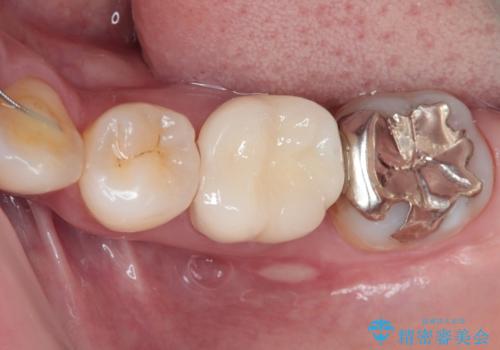

目立つ銀歯をオールセラミッククラウンで自然に|20代女性の審美補綴症例

- 矯正治療が終了し、歯並びが整ったことで左下の銀歯が目立つことを気にされてご来院されました。

「せっかく矯正できれいになったので、銀歯も自然な白い歯にしたい」というご希望でした。

患者様は根管治療のやり替えは希望されなかったため、ファイバーコア+オールセラミッククラウンによる補綴治療を行いました。